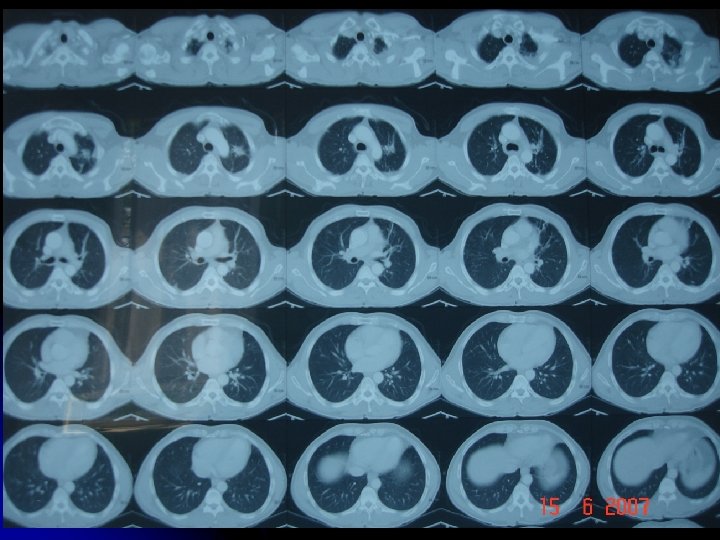

CÖ l 41 yaşında, işçi l Erkek l Doğum yeri: Gümüşhane l

l ŞİKAYETİ: Hemoptizi l 2006 şubat ayından beri tekrarlayan hemoptizi

l Özgeçmişi: Ø l 1997 - Tbc tanısıyla 6 ay tedavi Alışkanlıklar: Sigara 4 paket-yıl (7 yıldır içmiyor)

Balgamda Aside dirençli basil negatif l Kültürde M. Tuberculosis üremedi. l Orta sıklıkta PNL, az sayıda makrofaj l Atipik hücre görülmedi. l

l TORAKS BT (17/05/07): sol akciğer üst lob apikoposterior segment düzeyinde yaygın sekel fibrotik değişiklikler izlenmiştir. l BRONKOSKOPİ (22/02/07): Aktif kanama odağı saptanmadı

l Hastanın hemoptizilerinin tekrarlaması üzerine, hastaya 08/04/07 ve 11/05/07 tarihlerinde sol akciğer üst lob bronşial arterlerine embolizasyon uygulandı.

Ancak takiplerde hemoptizileri devam etti. l Kanama odağı? ? ? l

l Hastaya 07 -06 -2007’de sol akciğer üst lobektomi uygulandı. Lobektomi materyali patolojik inceleme için gönderildi.

l PATOLOJİ SONUCU: Sol Akciğer üst lobektomi materyali, kistik bronşiektazi, bu zeminde gelişmiş aspergilloma saptandı. l Hastaya İtraspor 100 mg tb 2 x 1 bir ay kullanmak üzere başlandı. itrakonazol